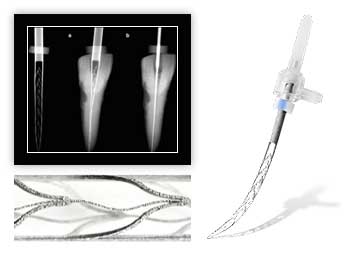

Наше оборудование